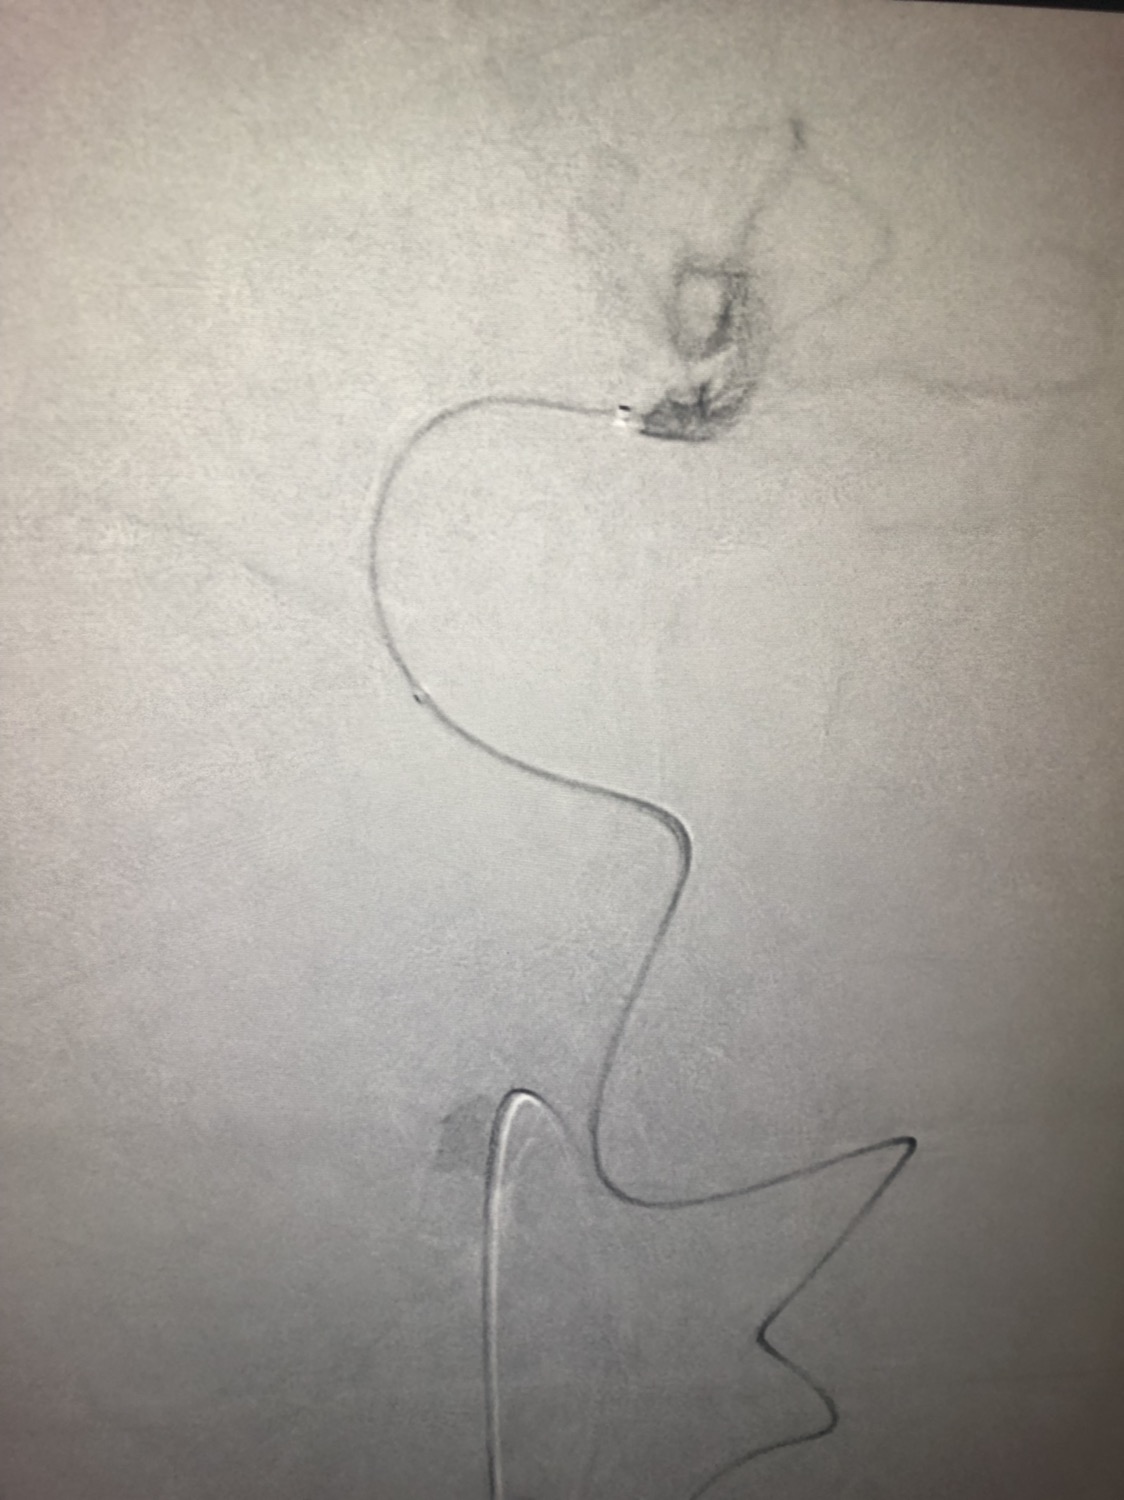

急诊二。zde,f53y。

意识模糊进行性加重8h,基底动脉闭塞,reco取栓再通,貌似动脉硬化,实际血管光滑。造影➕取栓8min。今日团队配合紧密,不到三小时全麻造影取栓带苏醒完成两台取栓。团队棒棒的!南阳市中心医院神经内科脑血管病介入团队